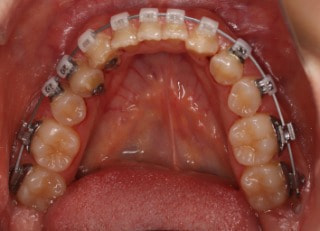

治療開始時